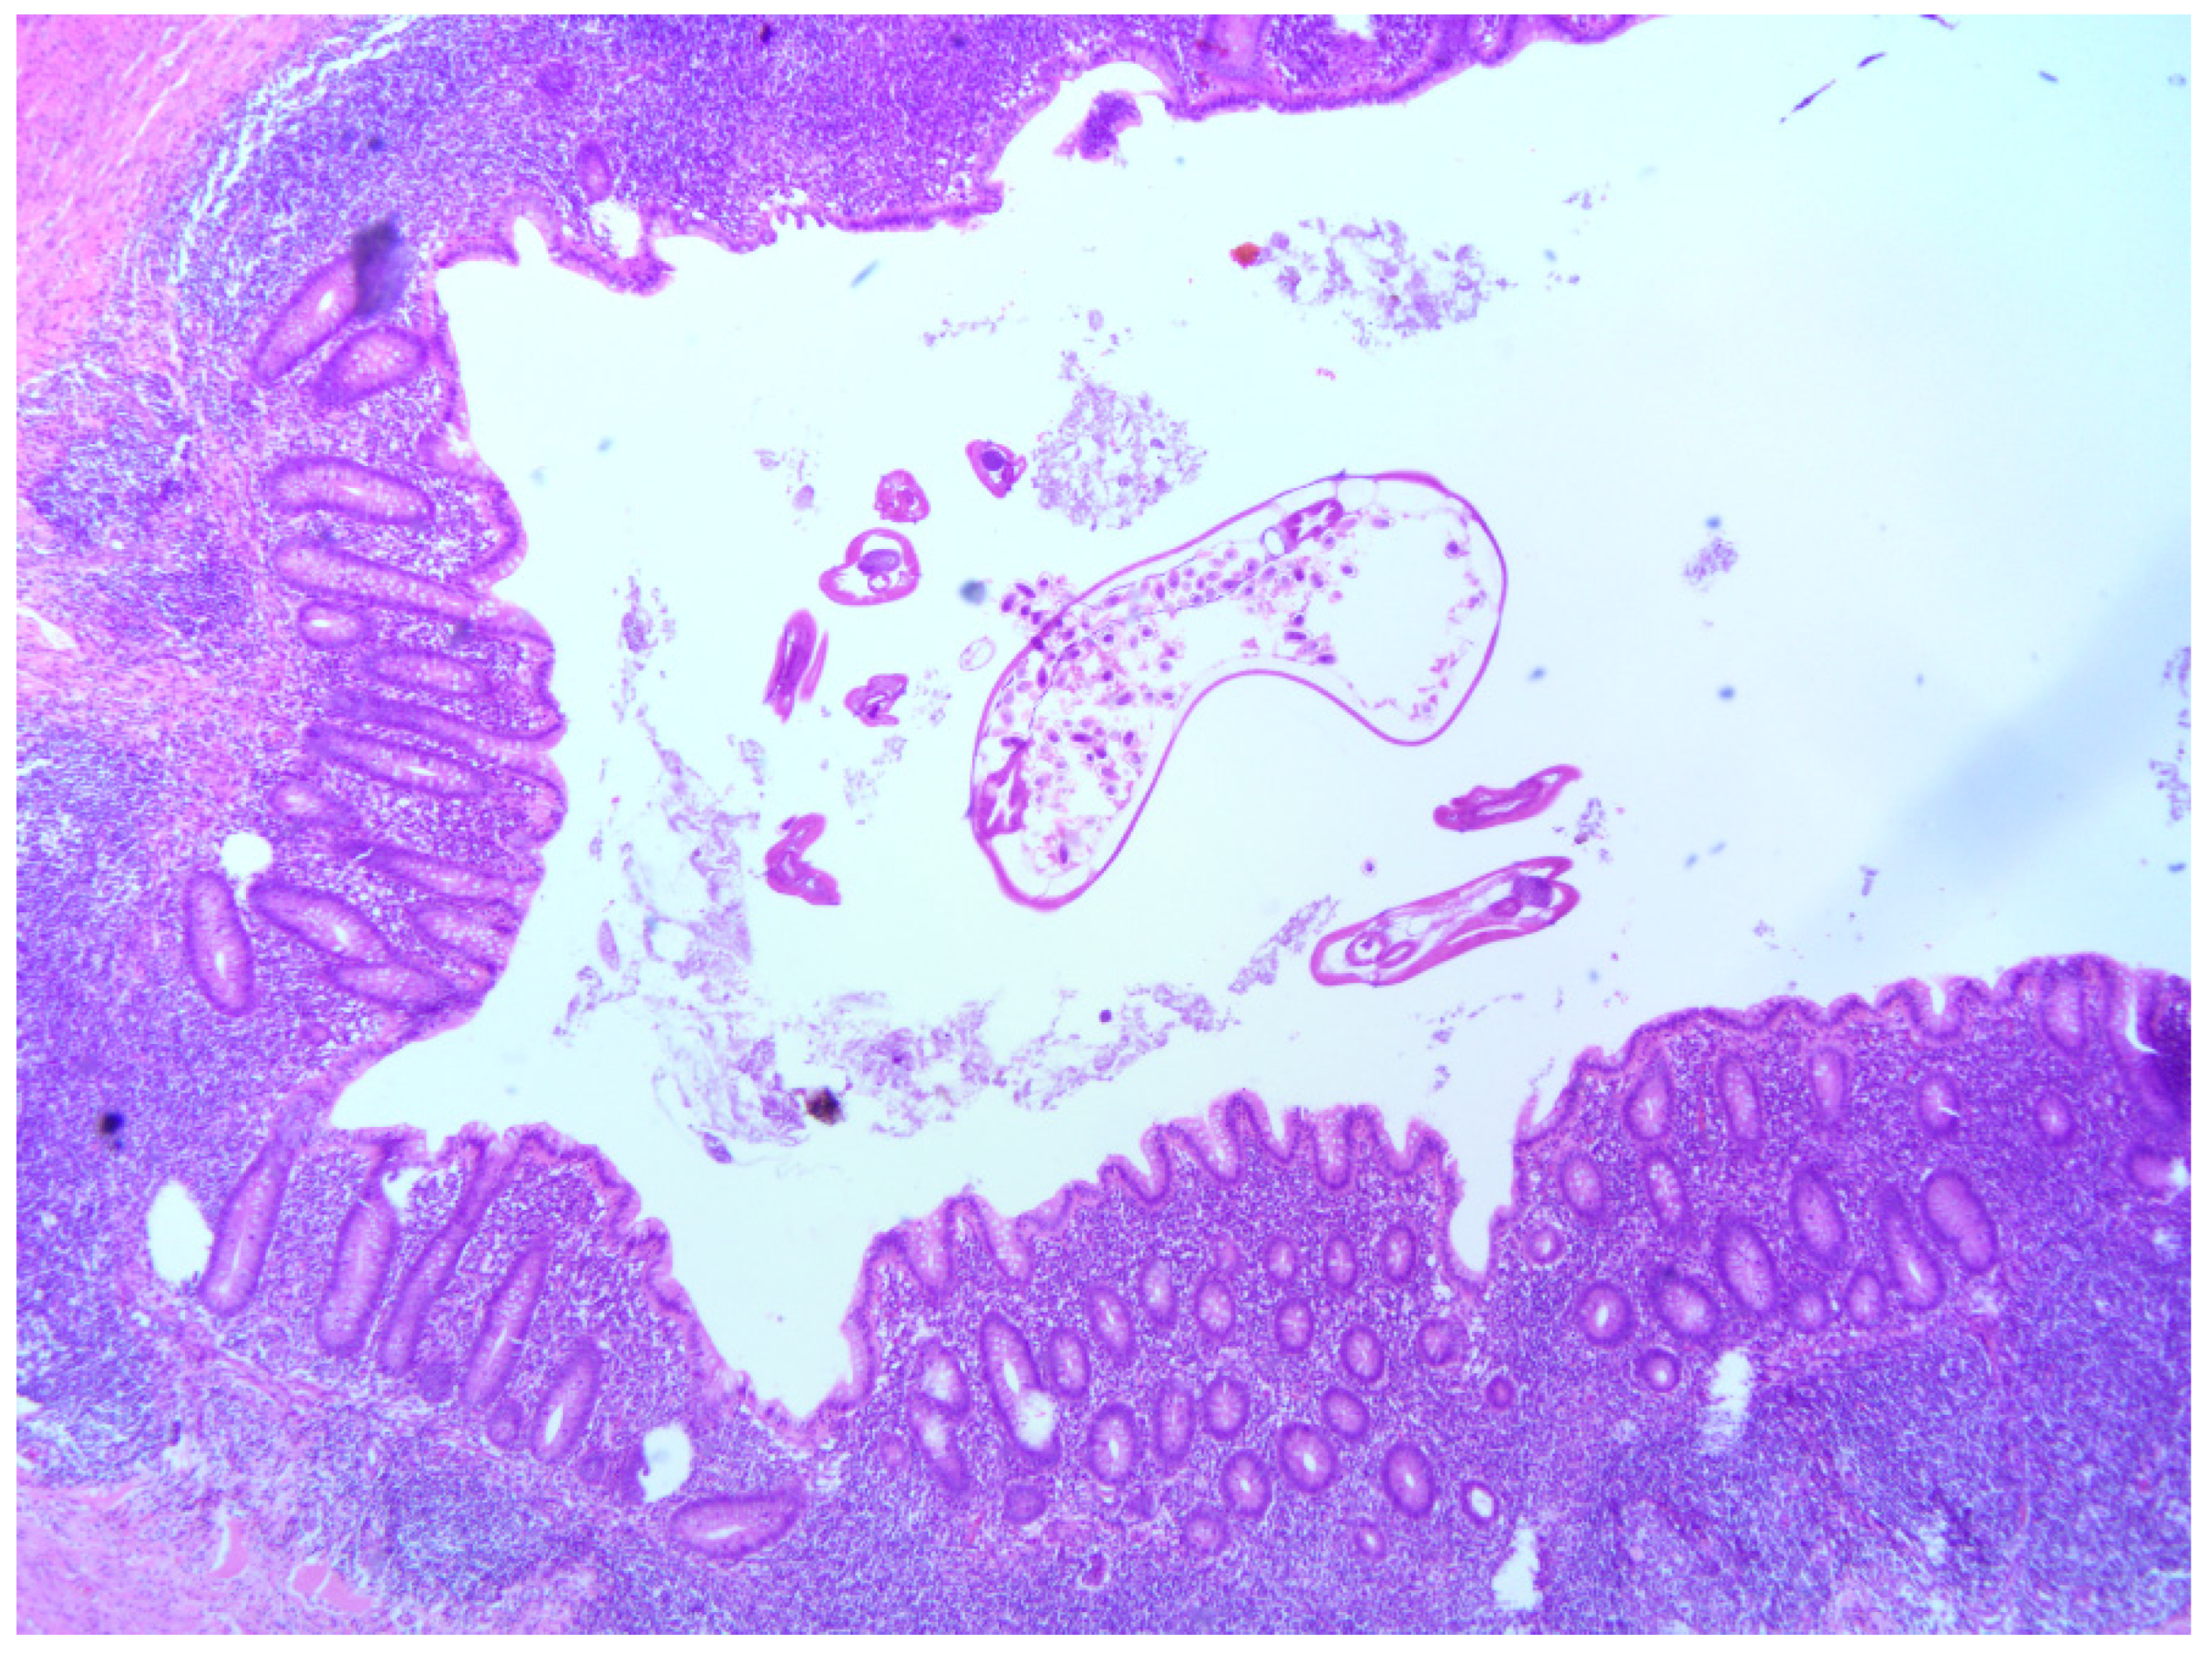

3.3. Histopathological Analysis of Samples with Appendiceal Enterobiasis